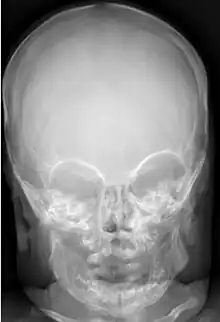

Macrocephaly is customarily diagnosed if head circumference is greater than two standard deviations (SDs) above the mean.[11] Relative macrocephaly occurs if the measure is less than two SDs above the mean, but is disproportionately above that when ethnicity and stature are considered. Diagnosis can be determined in utero or can be determined within 18–24 months after birth in some cases where head circumference tends to stabilize in infants.[12] Diagnosis in infants includes measuring the circumference of the child's head and comparing how significant it falls above the 97.5 percentile of children similar to their demographic. If falling above the 97.5th percentile then the patient will be checked to determine whether there is any intracranial pressure present and whether or not immediate surgery is needed.[2] If immediate surgery is not needed then further testing will be done to determine whether the patient has either macrocephaly or benign macrocephaly.

Diagnosis for macrocephaly involves the comparison of the infant's head circumference to that of other infants of the same age and ethnicity. If a patient is suspected of having macrocephaly molecular testing will be used to confirm diagnosis. Symptoms vary on the cause of macrocephaly on the child and if the child has any other accompanying syndromes which will be determined through molecular testing.

Benign macrocephaly can occur without reason or be inherited by one or both parents (in which it is considered benign familial macrocephaly and is considered megalencephaly form of macrocephaly). Diagnoses for familial macrocephaly is determined by measuring the head circumference of both parents and comparing it to the child's. Benign and familial macrocephaly is not associated with neurological disorders.[2] While benign and familial macrocephaly does not result in neurological disorders, neurodevelopment will still be assessed.